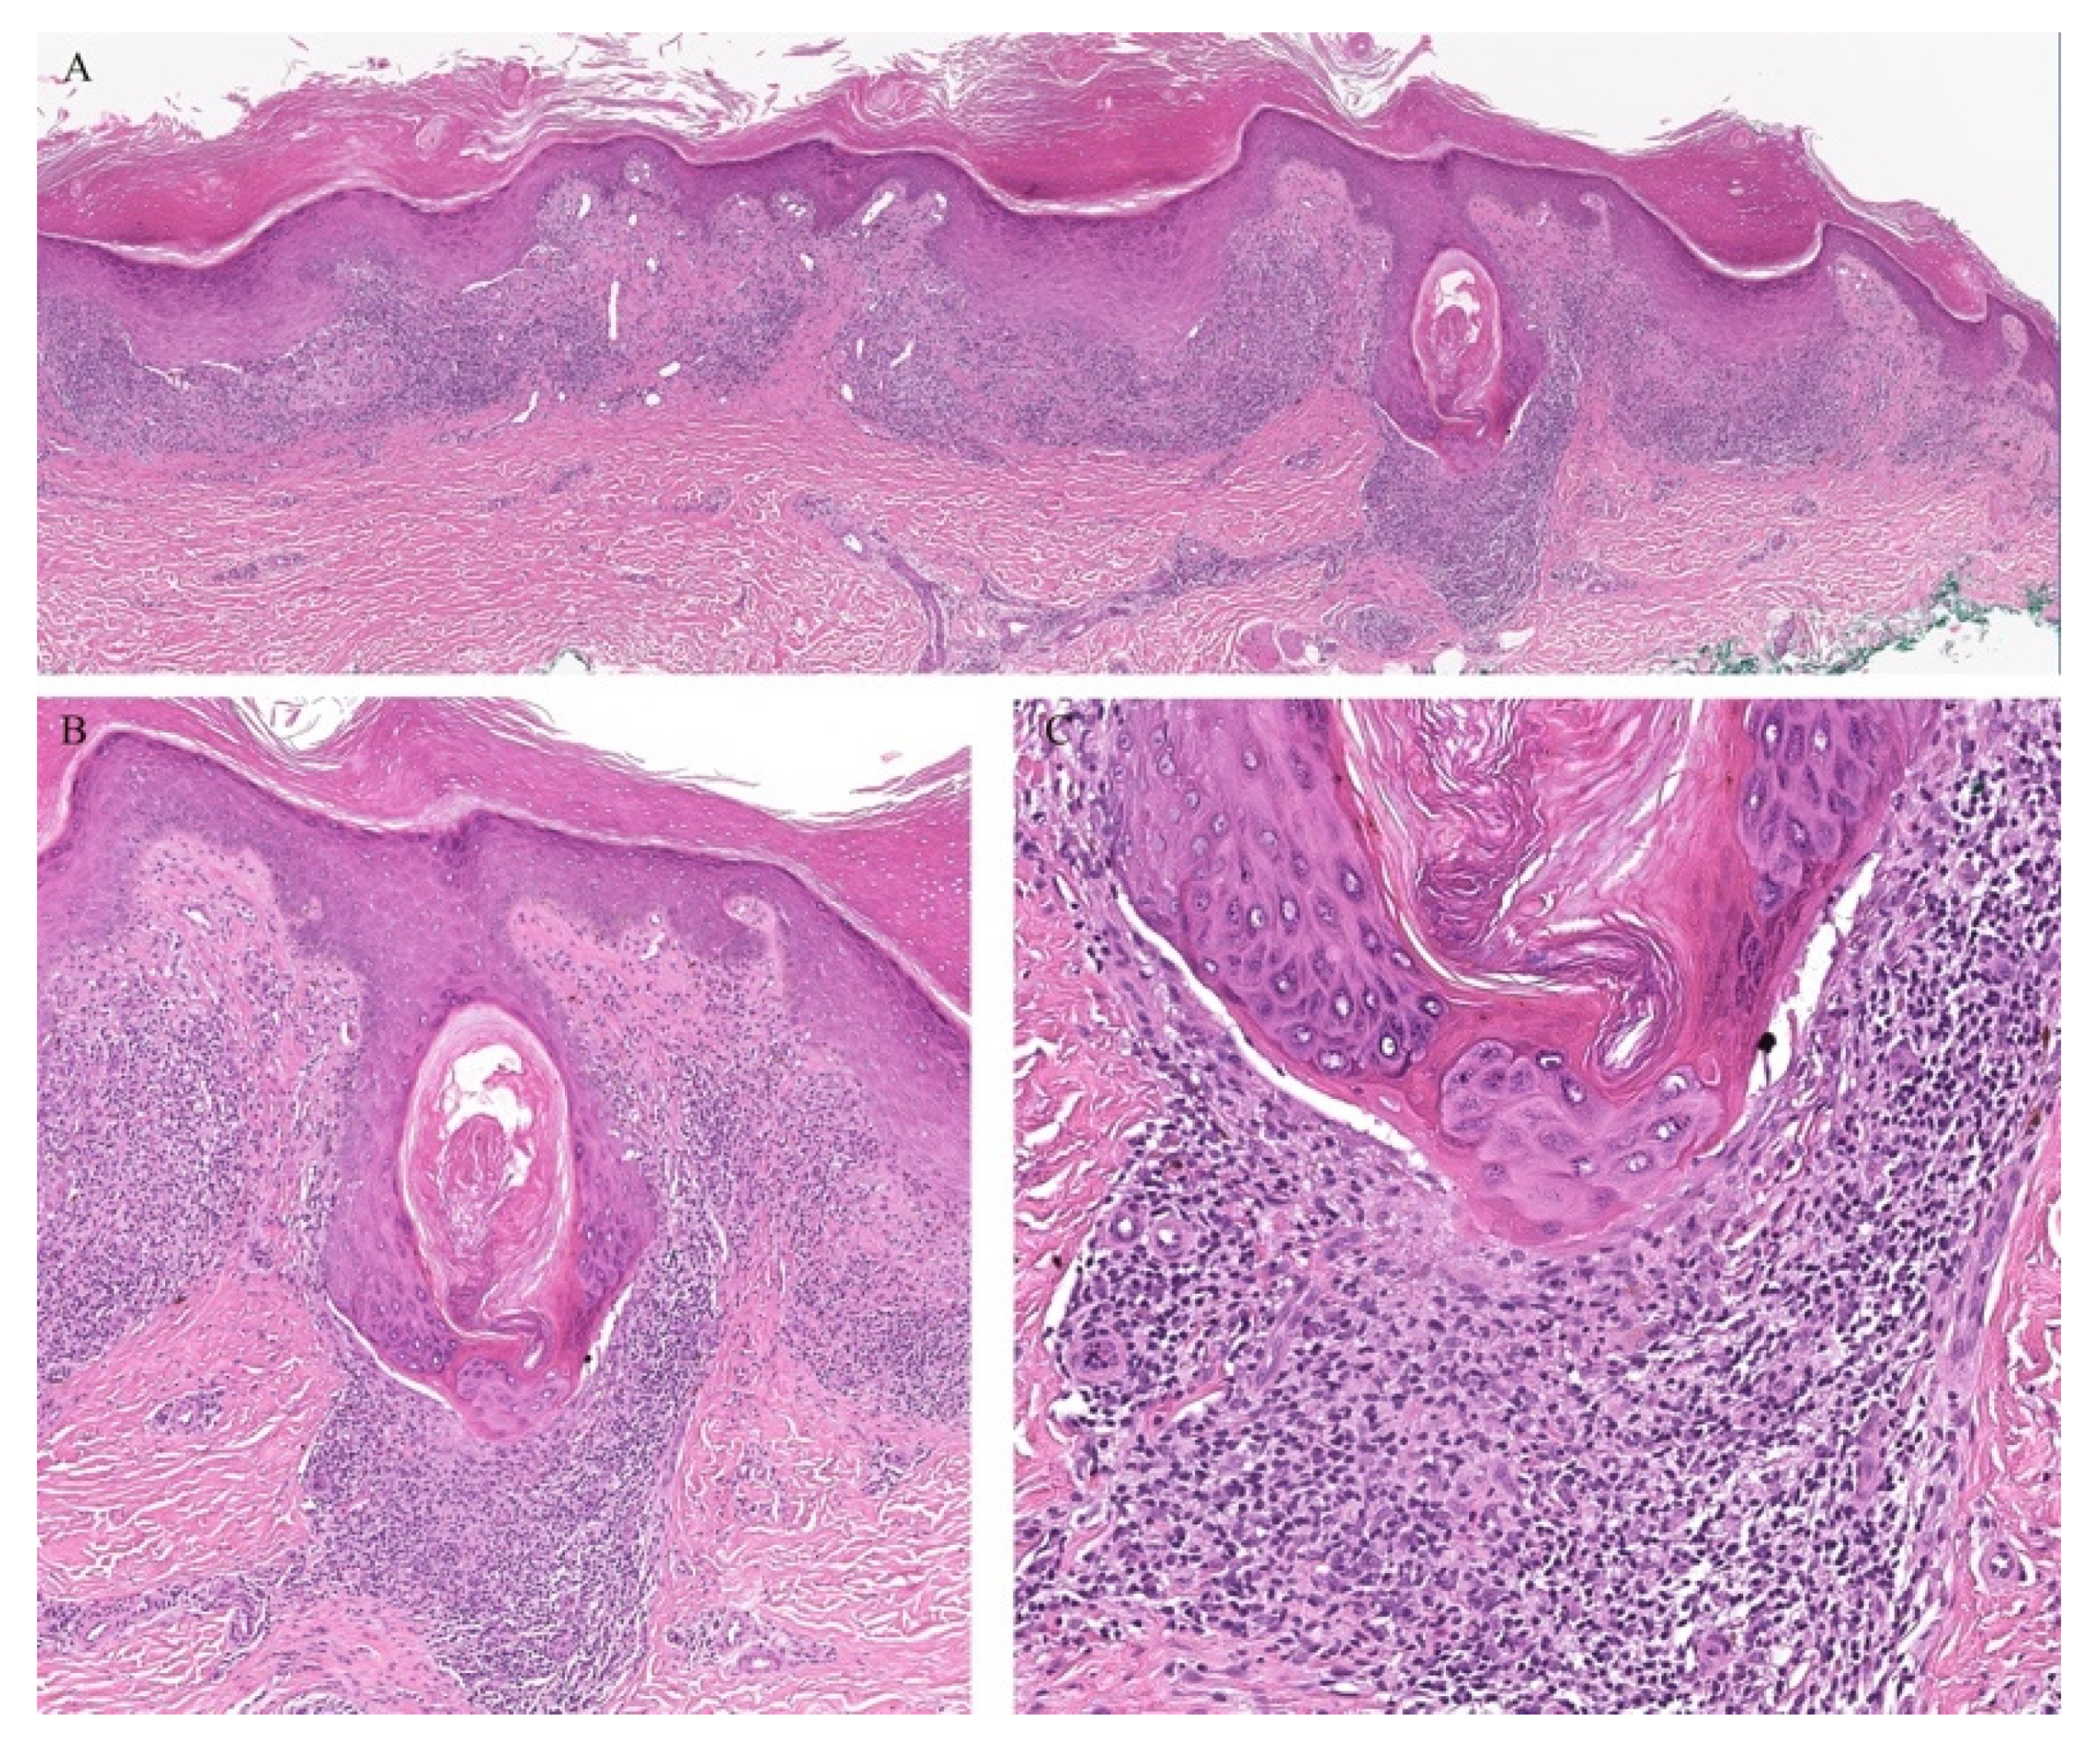

Lichen planus is the prototype lichenoid dermatitis characterized by a self-limiting eruption of pruritic flat-topped violaceous papules. On histopathology, hyperkeratosis, hypergranulosis, irregular acanthosis, and subepidermal clefts known as Max Joseph spaces are observed. A band-like lymphohistiocytic infiltrate is also seen. Distinct adnexotropic variants of lichen planus have been described (Figure 1). These include follicular lichen planus, lichen planus follicularis tumidus, and syringotropic lichen planus.

Figure 1.

(A–C) Lichen planus with follicular involvement.

Lichen planopilaris, or follicular lichen planus, is a distinct variant of lichen planus whereby inflammation is seen around the hair follicle both clinically and histologically (Figure 1). Clinically, this presents with perifollicular erythema, follicular keratotic plugs, and a scarring alopecia [1,2].

Lichen planus follicularis tumidus (LPFT) is another distinct adnexotropic variant of lichen planus. Clinically, it is characterized by the presence of typical lichen planus lesions with the addition of comedo-like lesions and keratin-filled cysts, most commonly located in the retroauricular area. Most patients have classical lichen planus lesions on other parts of the body. On histopathology, the typical features of lichen planus are seen along with the involvement of the hair follicle. Follicular hyperkeratosis is observed and the follicular infundibulum is cystic and dilated. The follicular infundibulum is also surrounded by a lichenoid infiltrate [3]. Recognizing this entity is important as the differential diagnosis includes cutaneous lupus erythematosus (LE) with cysts and comedones and follicular mycosis fungoides (MF). Cutaneous LE is characterized by increased mucin deposition not seen in LPFT, while the presence of epidermotropism and an infiltrate of atypical lymphocytes is noted in follicular MF and not in LPFT [4].